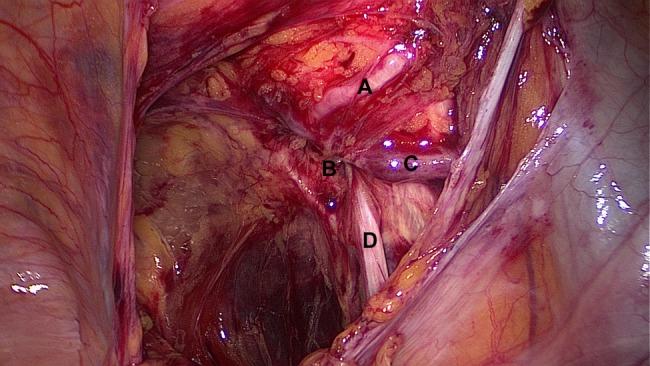

Obturator hernias are a rare form of abdominal wall hernias. We present a case of a patient with an obturator hernia diagnosed by the classical signs of lower abdominal pain, a positive Howship-Romberg sign (painful internal rotation of the hip) and a computed tomography scan showing a herniated loop of small bowel. During the emergency laparoscopic hernia repair (transabdominal preperitoneal approach) a variant vessel, the corona mortis, was detected.

闭孔疝是一种罕见的腹壁疝。我们报告一例闭孔疝患者,通过下腹部疼痛的典型体征、阳性豪希普-罗姆伯格征(髋关节疼痛性内旋)以及计算机断层扫描显示小肠疝出环而确诊。在急诊腹腔镜疝修补术(经腹腹膜前入路)过程中,发现了一条变异血管,即死亡冠。